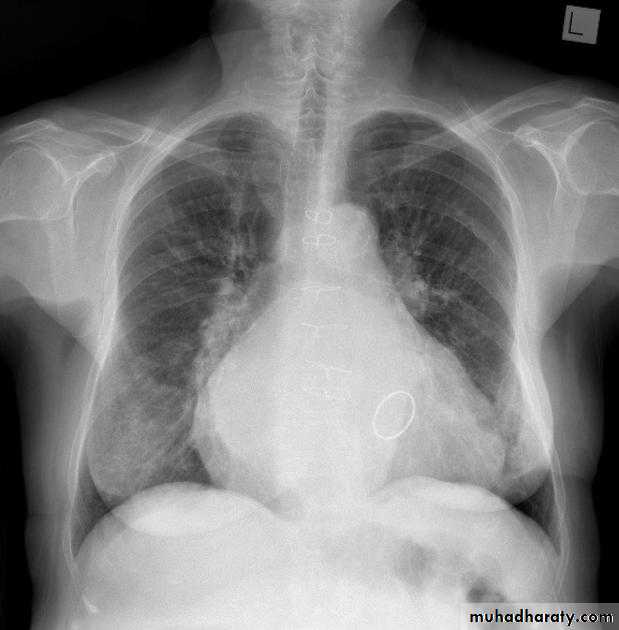

Pericardial effusion

occur when fluid collects in the pericardial space (a normal pericardial sac contains approximately 30-50 ml of fluid).radiographic features

Plain radiograph

a very small pericardial effusion can be occult on plain film, greater than 200 ml required to be visible radiographicly.

there can be globular enlargement of the cardiac shadow giving a water bottle configuration; known as Globe shape heart or pumpkin shape heart .